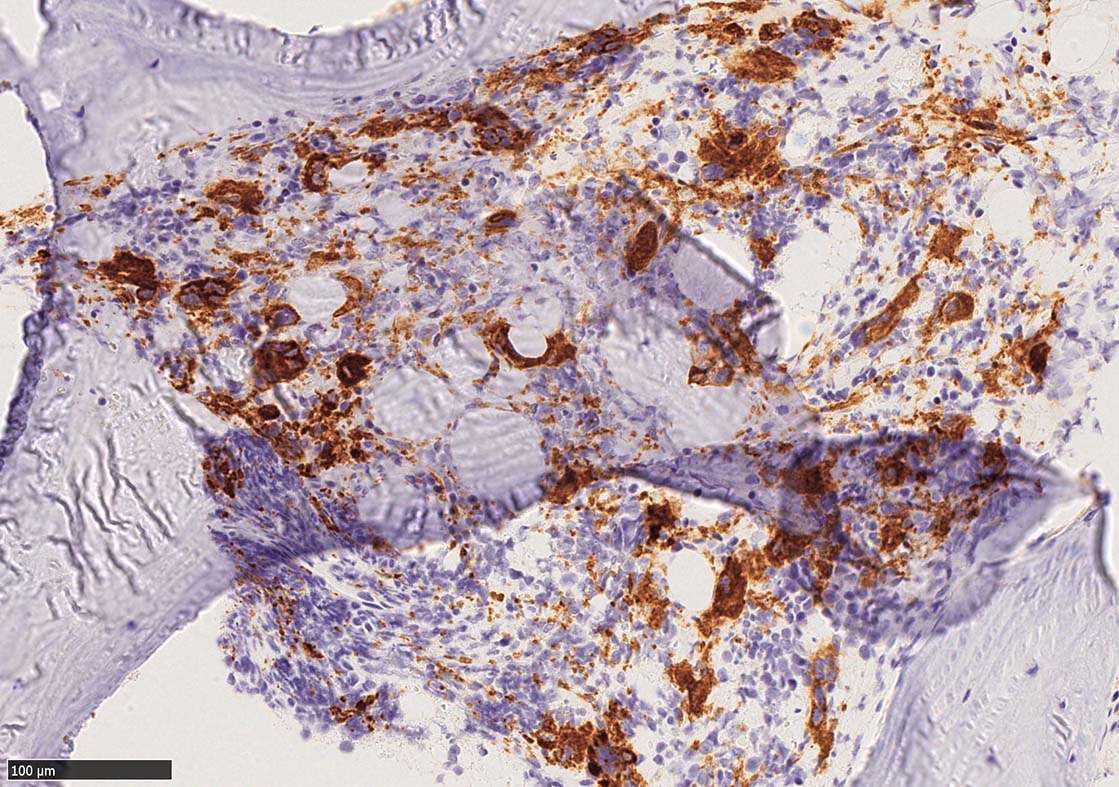

骨髄組織所見 bone marrow biopsy total 6mm in length

CD42b染色